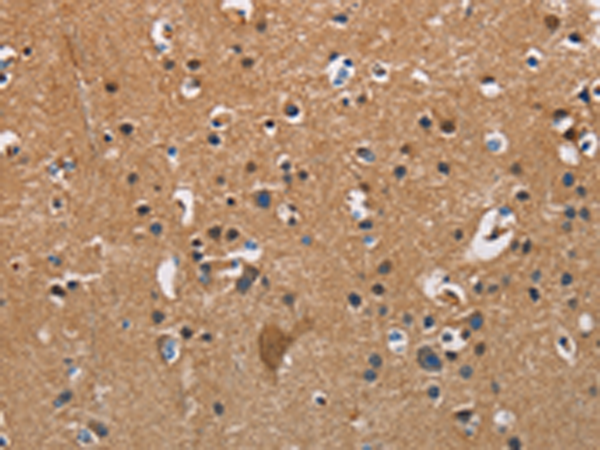

分类: 科研抗体货号: P06986别名:应用: IHC反应种属: Human